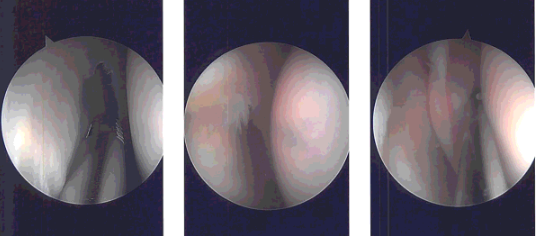

A medical entry portal was made using a spinal needle. Examination of the medial tibiofemoral compartment showed tears of the posterior body of the medial meniscus. The tear was cleaned using biters as well as shaver. were achieved. Examination of the Intercondylar notch showed intact ACL.

Examination of the lateral femoral condyle and lateral tibiofemoral compartment showed medial fraying of the lateral meniscus. Debridement was done using a shaver and biters.

Examination of the patellofemoral joint showed no chondral damage. There was chondral damage on the medial femoral condyle, which was cleaned using a shaver.

Intraoperative Arthroscopy Images